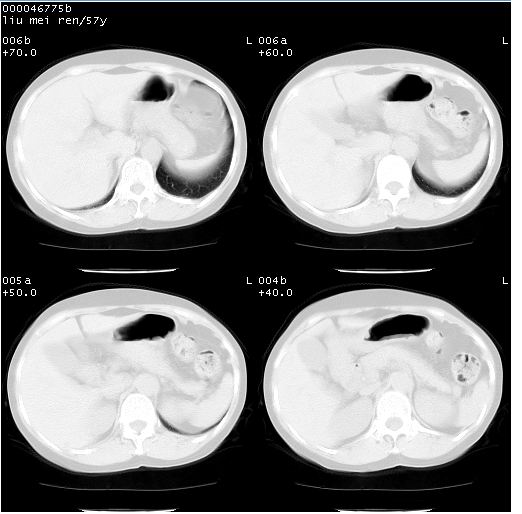

患者 女,57岁。因车祸受伤,其家属要求行“全身ct检查”。平素健康。

胸部ct轴位平扫(层厚10mm,螺距1.5,重建间隔10mm),图像如下: